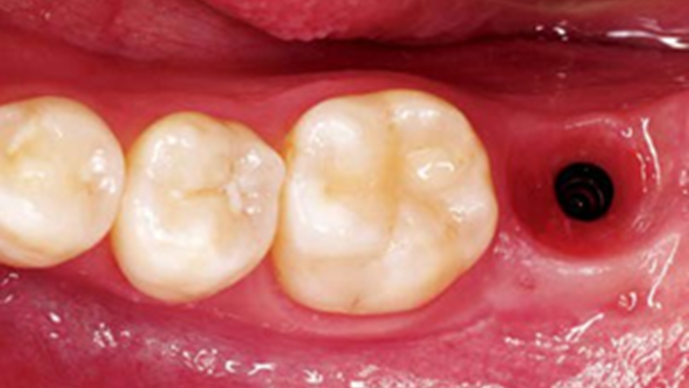

Clinical case: Bone filling into the bottom of deepest thread at 8.0mm AnyRidge fixture

- Courtesy of Dr. Kwang Bum Park -

Keywords

AnyRidge, Knifethread ,extraction socket, ,initial stability ,Allograft, ,osseointegratio ,Dr. Kwang Bum Park, , Mandibular, Single replacement, AnyRidge, Mega-oss,

Products used

Implant system-AnyRidge, Regeneration-Mega-Oss